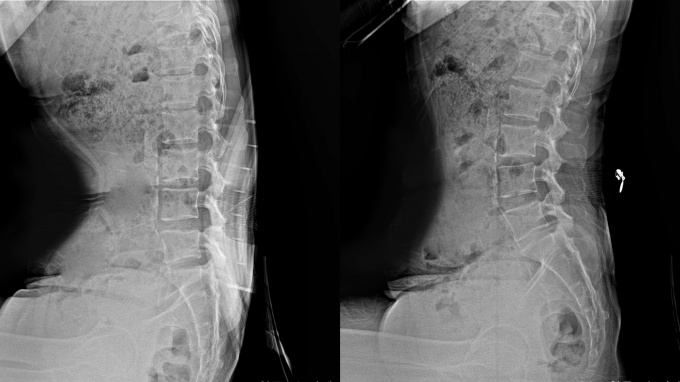

ÀÚ»ý ¸ÂÃã¹ÌÇÐ Ç㸮Äí¼ÇÀº ÀÇÀÚ µî¹ÞÀÌ¿¡ °íÁ¤ÇØ »ç¿ëÇÏ´Â Á¦Ç°À¸·Î, ÀÚ»ýÇѹ溴¿øÀÇ Ãß³ª¿ä¹ý ¿ø¸®¿¡ Âø¾ÈÇØ °³¹ßµÆ´Ù. ±âÁ¸ Ç㸮Äí¼Ç°ú Â÷º°È­µÈ ±â¼úÀ» ÅëÇØ ¾ÉÀº ÀÚ¼¼¿¡¼­ ôÃß°¡ °¡ÇØÁö´Â ÇÏÁßÀ» È¿°úÀûÀ¸·Î ºÐ»ê½ÃÄÑÁØ´Ù.

°¡Àå Å« Ư¡Àº Á¦Ç° Á߾Ӻο¡ À§Ä¡ÇÑ Èä¿äÃß¿¬Á¢ºÎ ¹Þħ´ë´Ù. Èä¿äÃß¿¬Á¢ºÎ¶õ ÈäÃß(µî»À)¿Í ¿äÃß(Ç㸮»À)°¡ À̾îÁö´Â ÁöÁ¡À¸·Î, µð½ºÅ© ÁúȯÀÌ °¡Àå ºó¹øÈ÷ ¹ß»ýÇÏ´Â ¿äÃß 4¹ø°ú 5¹ø ¿¬°áºÎÀ§¿¡¼­ 10~15cm ¶³¾îÁø °÷¿¡ À§Ä¡ÇØ ÀÖ´Ù.

ÀÚ»ý ¸ÂÃã¹ÌÇÐ Ç㸮Äí¼ÇÀº ÀÌ Èä¿äÃß¿¬Á¢ºÎ¸¦ È¿°úÀûÀ¸·Î ÁöÁöÇØÁÜÀ¸·Î½á üÁß ºÐ»êÀ» µ½°í ¿äÃ߸¦ ½ÅÀå½ÃÄÑ Ã´Ãß¿¡ °¡ÇØÁö´Â ¾Ð¹ÚÀ» ÇØ¼Ò½ÃÄÑÁØ´Ù.

½ÇÁ¦ Ãß³ª¿ä¹ý¿¡¼­µµ Èä¿äÃß¿¬Á¢ºÎ´Â ôÃßÁúȯ Ä¡·á ½Ã Áß¿äÇÏ°Ô ¿©°ÜÁö´Â ºÎÀ§·Î Ʋ¾îÁø Èä¿äÃß¿¬Á¢ºÎ À§Ä¡¸¦ ¿Ã¹Ù¸£°Ô µÇµ¹·Á ôÃ߸¦ ºñ·ÔÇØ ÁÖº¯ ½Å°æ°ú ±ÙÀ°ÀÌ ¹Þ´Â ¾Ð¹ÚÀ» ÇØ¼Ò½ÃŲ´Ù.